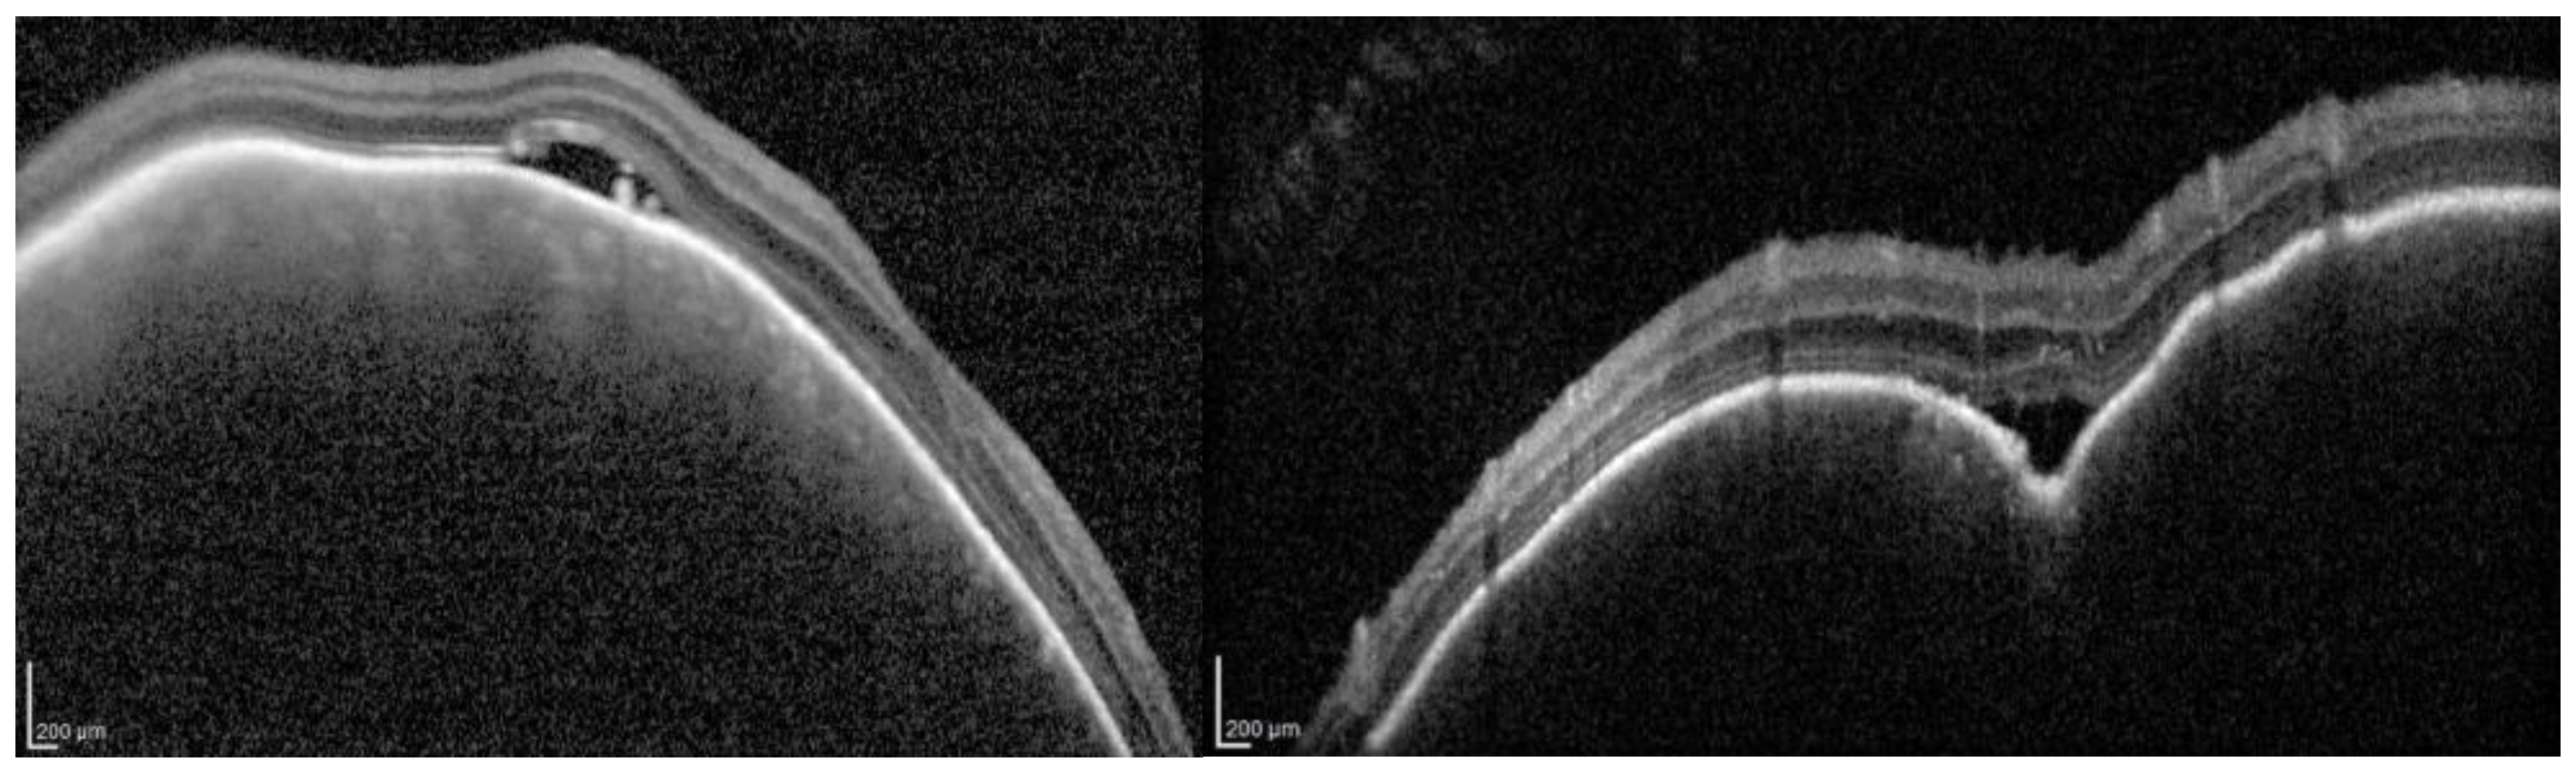

- Cacciamani, A.; Scarinci, F.; Parravano, M.; Giorno, P.; Varano, M. Choroidal thickness changes with photodynamic therapy for a diffuse choroidal hemangioma in Sturge–Weber syndrome. Int. Ophthalmol. 2014, 34, 1131–1135. [Google Scholar] [CrossRef] [PubMed]

- Spaide, R.F.; Koizumi, H.; Pozzoni, M.C. Enhanced depth imaging spectral-domain optical coherence tomography. Am. J. Ophthalmol. 2008, 146, 496–500. [Google Scholar] [CrossRef] [PubMed]

- Margolis, R.; Spaide, R.F. A pilot study of enhanced depth imaging optical coherence tomography of the choroid in normal eyes. Am. J. Ophthalmol. 2009, 147, 811–815. [Google Scholar] [CrossRef] [PubMed]

- Arora, K.S.; Quigley, H.A.; Comi, A.M.; Miller, R.B.; Jampel, H.D. Increased choroidal thickness in patients with Sturge-Weber syndrome. JAMA Ophthalmol. 2013, 131, 1216–1219. [Google Scholar] [CrossRef] [PubMed]

- Surve, A.; Azad, S.; Venkatesh, P.; Kumar, V.; Chawla, R.; Gupta, V.; Vohra, R. Choroidal Vascular Pattern in Cases of Sturge-Weber Syndrome. Ophthalmol Retin. 2019, 3, 1091–1097. [Google Scholar] [CrossRef] [PubMed]

- Ciancimino, C.; Di Pippo, M.; Rullo, D.; Ruggeri, F.; Grassi, F.; Scuderi, G.; Abdolrahimzadeh, S. An Update on Multimodal Ophthalmological Imaging of Diffuse Choroidal Hemangioma in Sturge-Weber Syndrome. Vision 2023, 7, 64. [Google Scholar] [CrossRef] [PubMed] [PubMed Central]